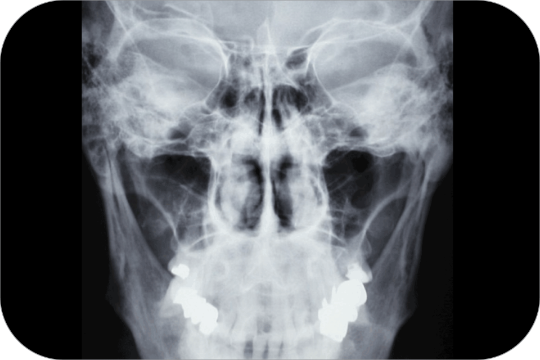

Senos Paranasales